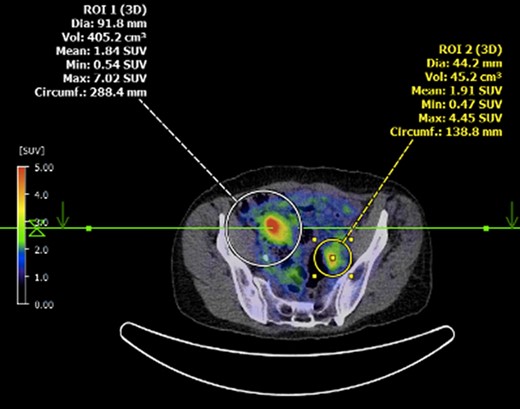

Submucosal biopsies from ascending colon unexpectedly demonstrated metastatic carcinoma consistent with female genital tract origin—CK7 positive; CK20 negative; PAX-8/WT-1/ER/CA125 all positive. A PET/CT was performed on the basis of the histological findings, which demonstrated intense FDG-avidity in the known site of disease in the ascending colon (Figs 2 and 3), as well as a separate focus of increased metabolism in the left pelvic side-wall (Fig. 4), which was presumed to represent an ovarian primary. There was no evidence of nodal or peritoneal disease, however, note was made of mild bilateral hydroureter without clear transition point. CA125 was 118 U/mL (Ref. range 0–35).

Axial PET showing separate focus of avidity in left pelvic side-wall.